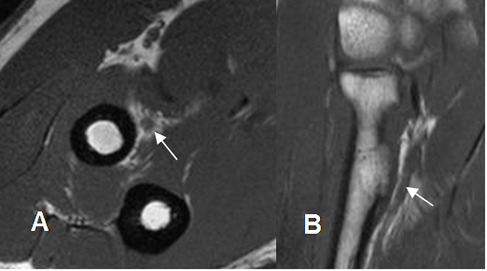

La inserción del tendón del tríceps en el olécranon, se observa mejor en secuencias sagitales. (3). Muestra estriaciones a nivel de su inserción, por interposición de grasa entre los fascículos. (8). (Fig 12 y 13). Puede encontrarse laxitud del tendón en extensión completa del codo, que no debe confundirse con ruptura y se confirma valorando las imágenes axiales. (8). (Fig 14).

Fig 14. Tendón del tríceps normal en RM.

Laxitud del tendón en secuencia T2, pero conserva su SI.